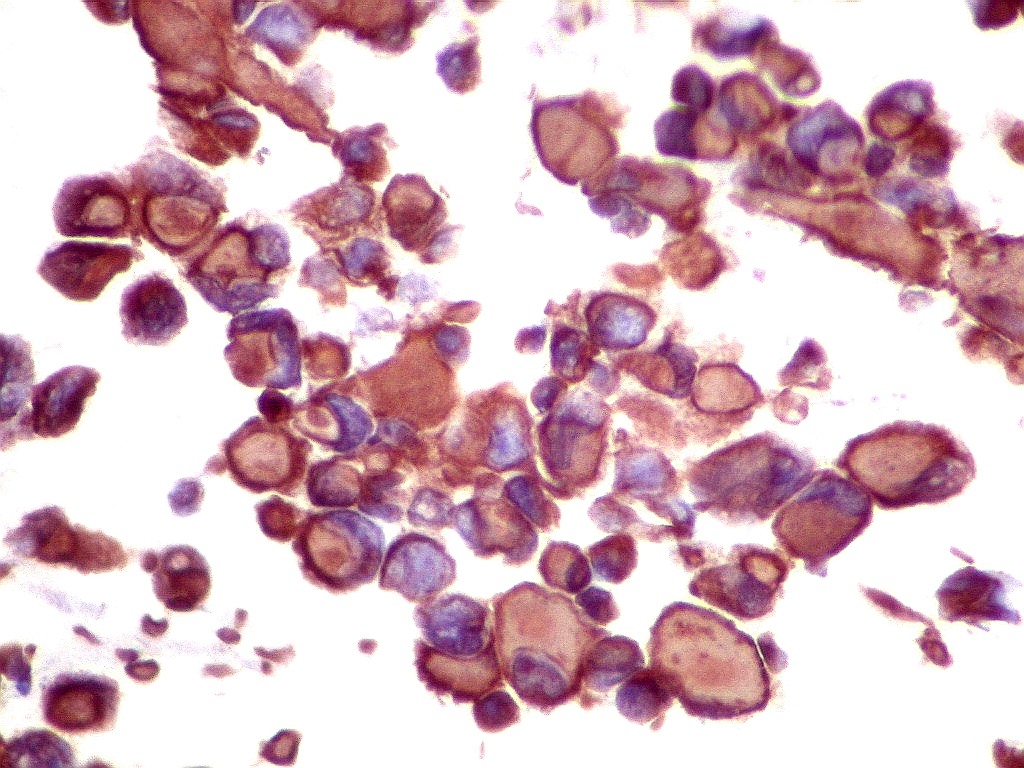

Tumor teratóide rabdóide atípico de III ventrículo.

2. Vimentina, GFAP.

Vimentina.   Filamento intermediário ubiquitário, presente em tecidos de várias linhagens. Aqui expressada nas células tumorais e no tecido nervoso, inclusive em células ependimárias.